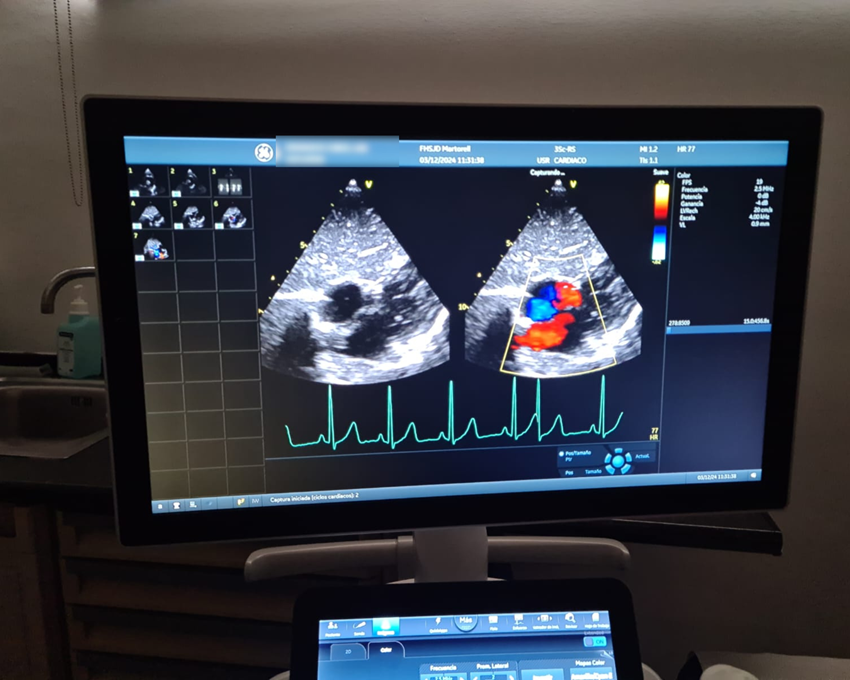

Fruit de la col·laboració multidisciplinària entre els clínics i els departaments tècnics d’aplicacions i sistemes hospitalaris, la unitat de cardiologia pediàtrica de la Fundació Hospital Sant Joan de Déu de Martorell (FHSJDM) ha vinculat el seu sistema de visualització d’estudis ecocardiogràfics amb el servei de cardiologia pediàtrica de l’Hospital Sant Joan de Déu Barcelona (HSJD) a Esplugues de Llobregat.

Gràcies a aquesta integració tecnològica, els equips mèdics podran compartir estudis ecocardiogràfics en temps real, millorant l’eficiència en el diagnòstic i tractament de les patologies cardíaques infantils. Aquest avenç permetrà que els professionals d’ambdós hospitals puguin intercanviar coneixements i consultar casos complexes amb referents de patologia.